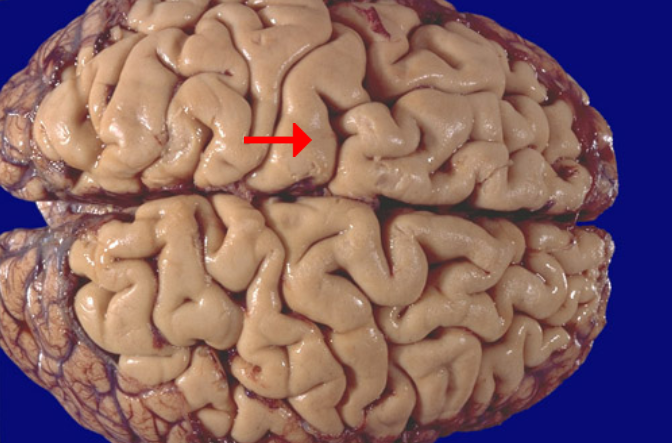

Sylvian fissure

Superior temporal gyrus

Middle temporal gyrus

Inferior temporal gyrus

Precentral gyrus (primary motor cortex)

Precentral gyrus (primary motor cortex)

Postcentral gyrus